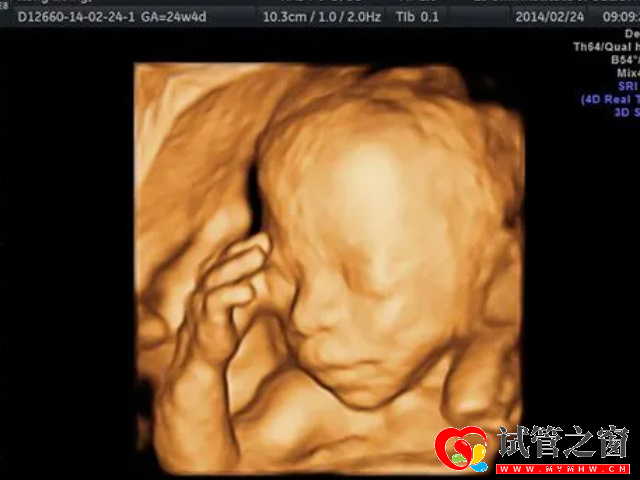

一般在怀孕22-24周左右,就需要上医院进行四维彩超,而四维检查主要就是检测胎儿是否存在畸形的一项重要孕检项目,为早期诊断胎儿先天性体表畸形和先天性心脏提供准确的科学依据。而且,从医学角度去看,通过四维也是可以看出胎儿是男是女的,不过医学上面是禁止医生给孕妈妈透露胎儿性别的,所以想要从医生方面去知晓是行不通的。不过在网络上,很多宝妈根基自身的实际情况总结出来通过四维检查看男女的小诀窍,比如说通过检查单上面的胎儿面相就能看出,大家感兴趣的话可以进行了解。

四维B超主要就是用来排畸的,在22-24周左右检查,因为这个时候胎儿的肢体及各主要脏器已经全部发育,而且羊水较适合做胎儿畸形筛查。重点是观察胎儿双眼与眼眶是否等大、等圆,以及眼距测量,硬腭及上唇弧形曲线是否连续中断等。顺着头部筛查胎宝宝的颈部,看是否有异常包块。

如果说你在检查的时候,看见自家宝宝面相是清秀的,大概率是男孩;如果鼻子大,嘴大的话,就是女孩。如果检查的时候没有看清楚,后期可以通过四维检查单子进行观察。

单纯就报告而言,胎儿排畸检查的报告上通常会有一张宝宝面部的三维图,不会有外生殖器的图出现在报告上的,而民间所总结的关于通过四维彩超判断生男生女的方法各种各样,也有很多宝妈证实过,所以关于四维看男女准确率可以参考下面。